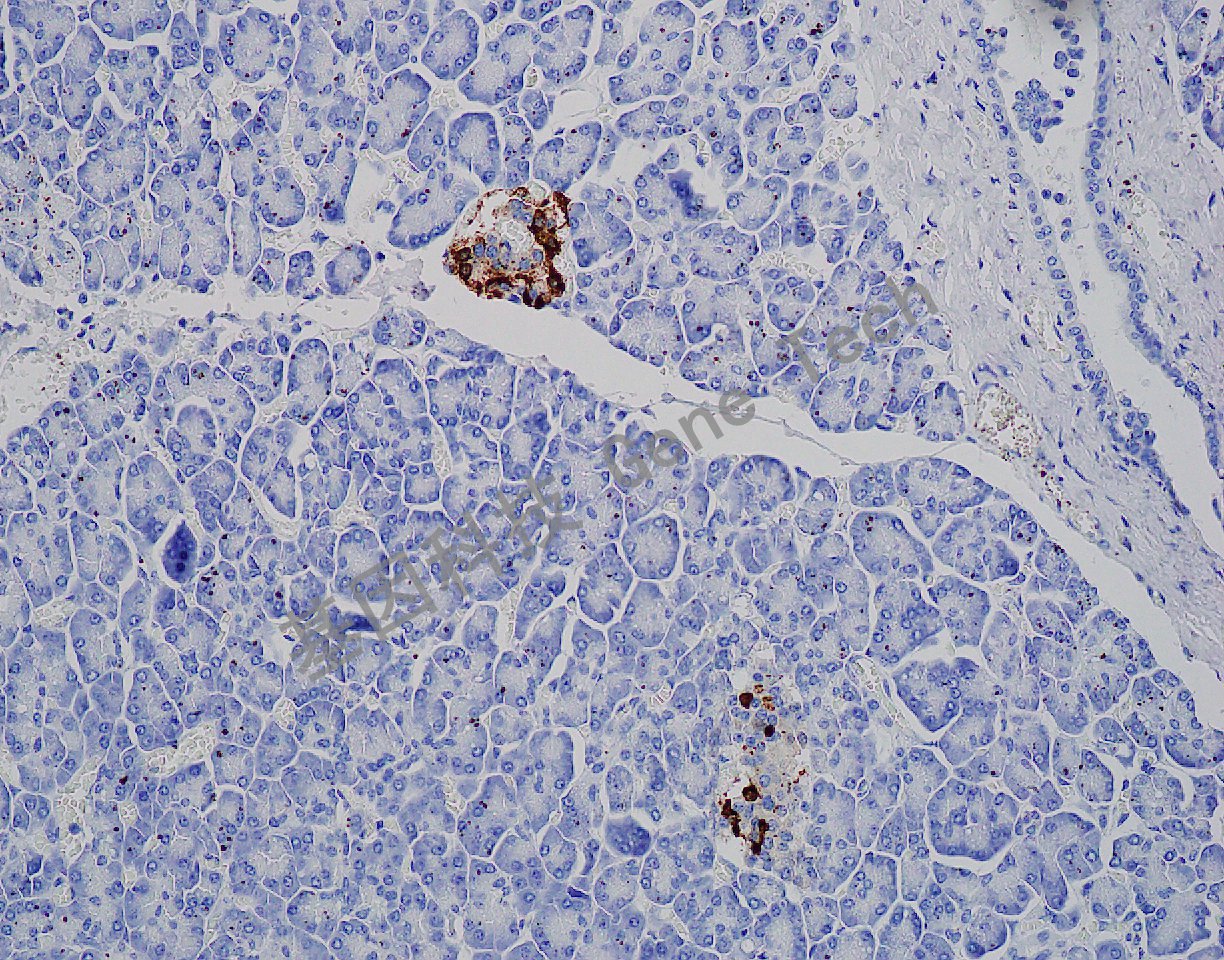

| 預處理:高pH熱修復 | 陽性部位:細胞漿 | 陽性對照:胰腺 |

| 簡介:Somatostatin(生長抑素)是胰島D細胞分泌的一種多肽激素,主要作用是抑制各種垂體激素的分泌、對胃腸運動與消化道激素的分泌也有一定的抑制作用等。表達于下丘腦、胃腸道、支氣管、唾液腺和胸腺內分泌細胞及部分甲狀腺C細胞。主要用于胰島細胞的功能性分類和消化道粘膜中內分泌細胞及腫瘤的研究。 | ||

| 胰腺石蠟切片,用 Somatostatin(GA0566)染色,細胞漿陽性,DAB 顯色。 | ||